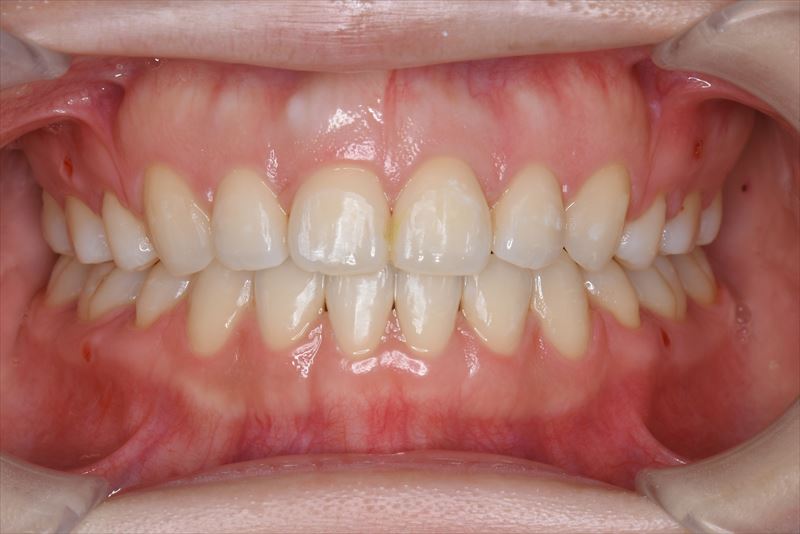

治療後

臼歯のみの咬合、口唇の閉鎖が難しい状況でした。抜歯を行い前歯を牽引することで、良好な側貌と緊密な咬合を獲得できました。